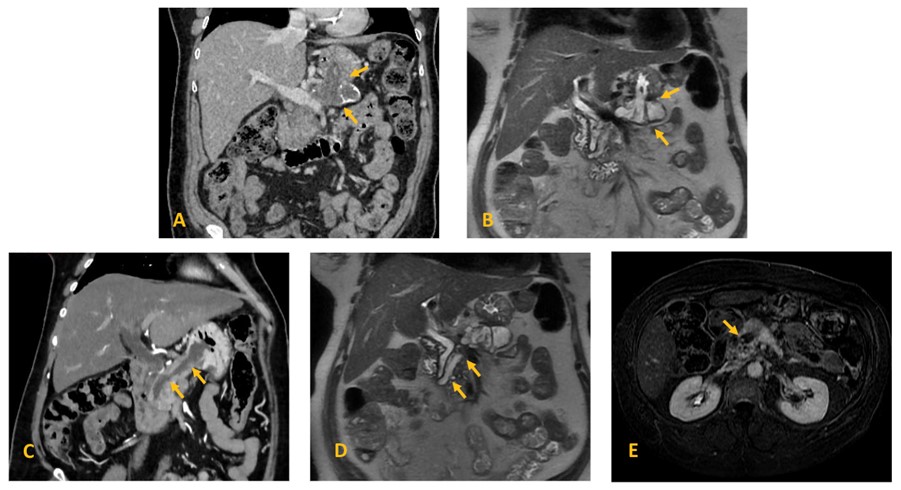

In our institution, a Magnetic Resonance Imaging (MRI) and a Computed Tomography (CT) scan revealed a 13 mm dilation of the main pancreatic duct (MPD) (Figure 1 C, D, E) and adjacent cystic lesions (one represented in Figure 1 A,B) in keeping with mixed-type intraductal papillary mucinous neoplasm (MT-IPMN); two wide communication tracts/fistulas with the stomach were confirmed (Figure 1 A,B,C); enhancing mural nodules were present in the MPD (one represented in Figure 1 E). CT scan also revealed abutment of the mesoportal confluence and hepatic artery and occlusion of the splenic vein. Celiac trunk and superior mesenteric artery were not involved (not shown).

Figure 1: Mixed-type IPMN with two gastropancreatic fistulas in a 69-year-old woman. Coronal (A) contrast-enhanced CT and (B) T2-weighted MR image of a pancreatic cyst with a fistulous tract into the stomach (arrows); (C) contrast-enhanced CT and (D) T2-weighted MR image demonstrate massive dilatation of the main pancreatic duct, with a fistulous tract into the stomach (arrows); (E) Axial contrast-enhanced fat-suppressed T1-weighted MR image on the transitional-phase demonstrate an enhancing nodule within the MD cyst (arrow).